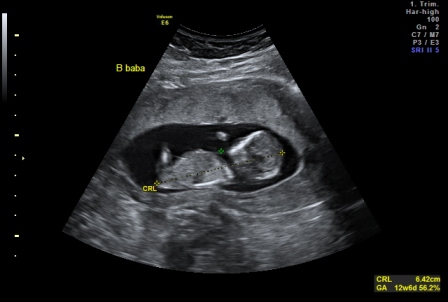

Szandra: Akkor szigorúan tartsd be amit mondanak. Vigyáz a babádra nagyon!!! És a kórházban mit csináltak veled? Infúziót kaptál? Vagy csak megvizsgáltak? ÉS eddig nem látták, hogy lehet hogy két baba van?